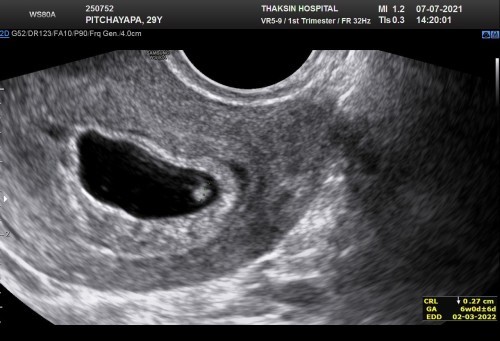

6w ภาวะแท้งคุกคาม

ไปซาวด์ทางช่องคลอด 6 w เห็นแต่หัวใจน้องกระพริบ แต่ยังไม่เจอเสียงหัวใจเลยคะ แล้วตอนนี้ เกิดภาวะแท้งคุกคาม เลือดออกทุกวัน หมอฉีดยากันแท้งให้ 1 เข็ม น้องจะเป็นอะไรมั้ยคะ ลุ้นๆมากเลยคะ ขอคำแนะนำจาก แม่ๆหน่อยคะ

หัวใจกระพริบ คือหัวใจเต้นอยู่ค่ะ ครรภ์อ่อนขนาดนี้เปิดฟังเสียงไม่ได้ค่ะอันตราย มันเป็นคลื่น ต้อง 10 วีค หน่อยค่อยฟังเสียงจะได้ปลอดภัย